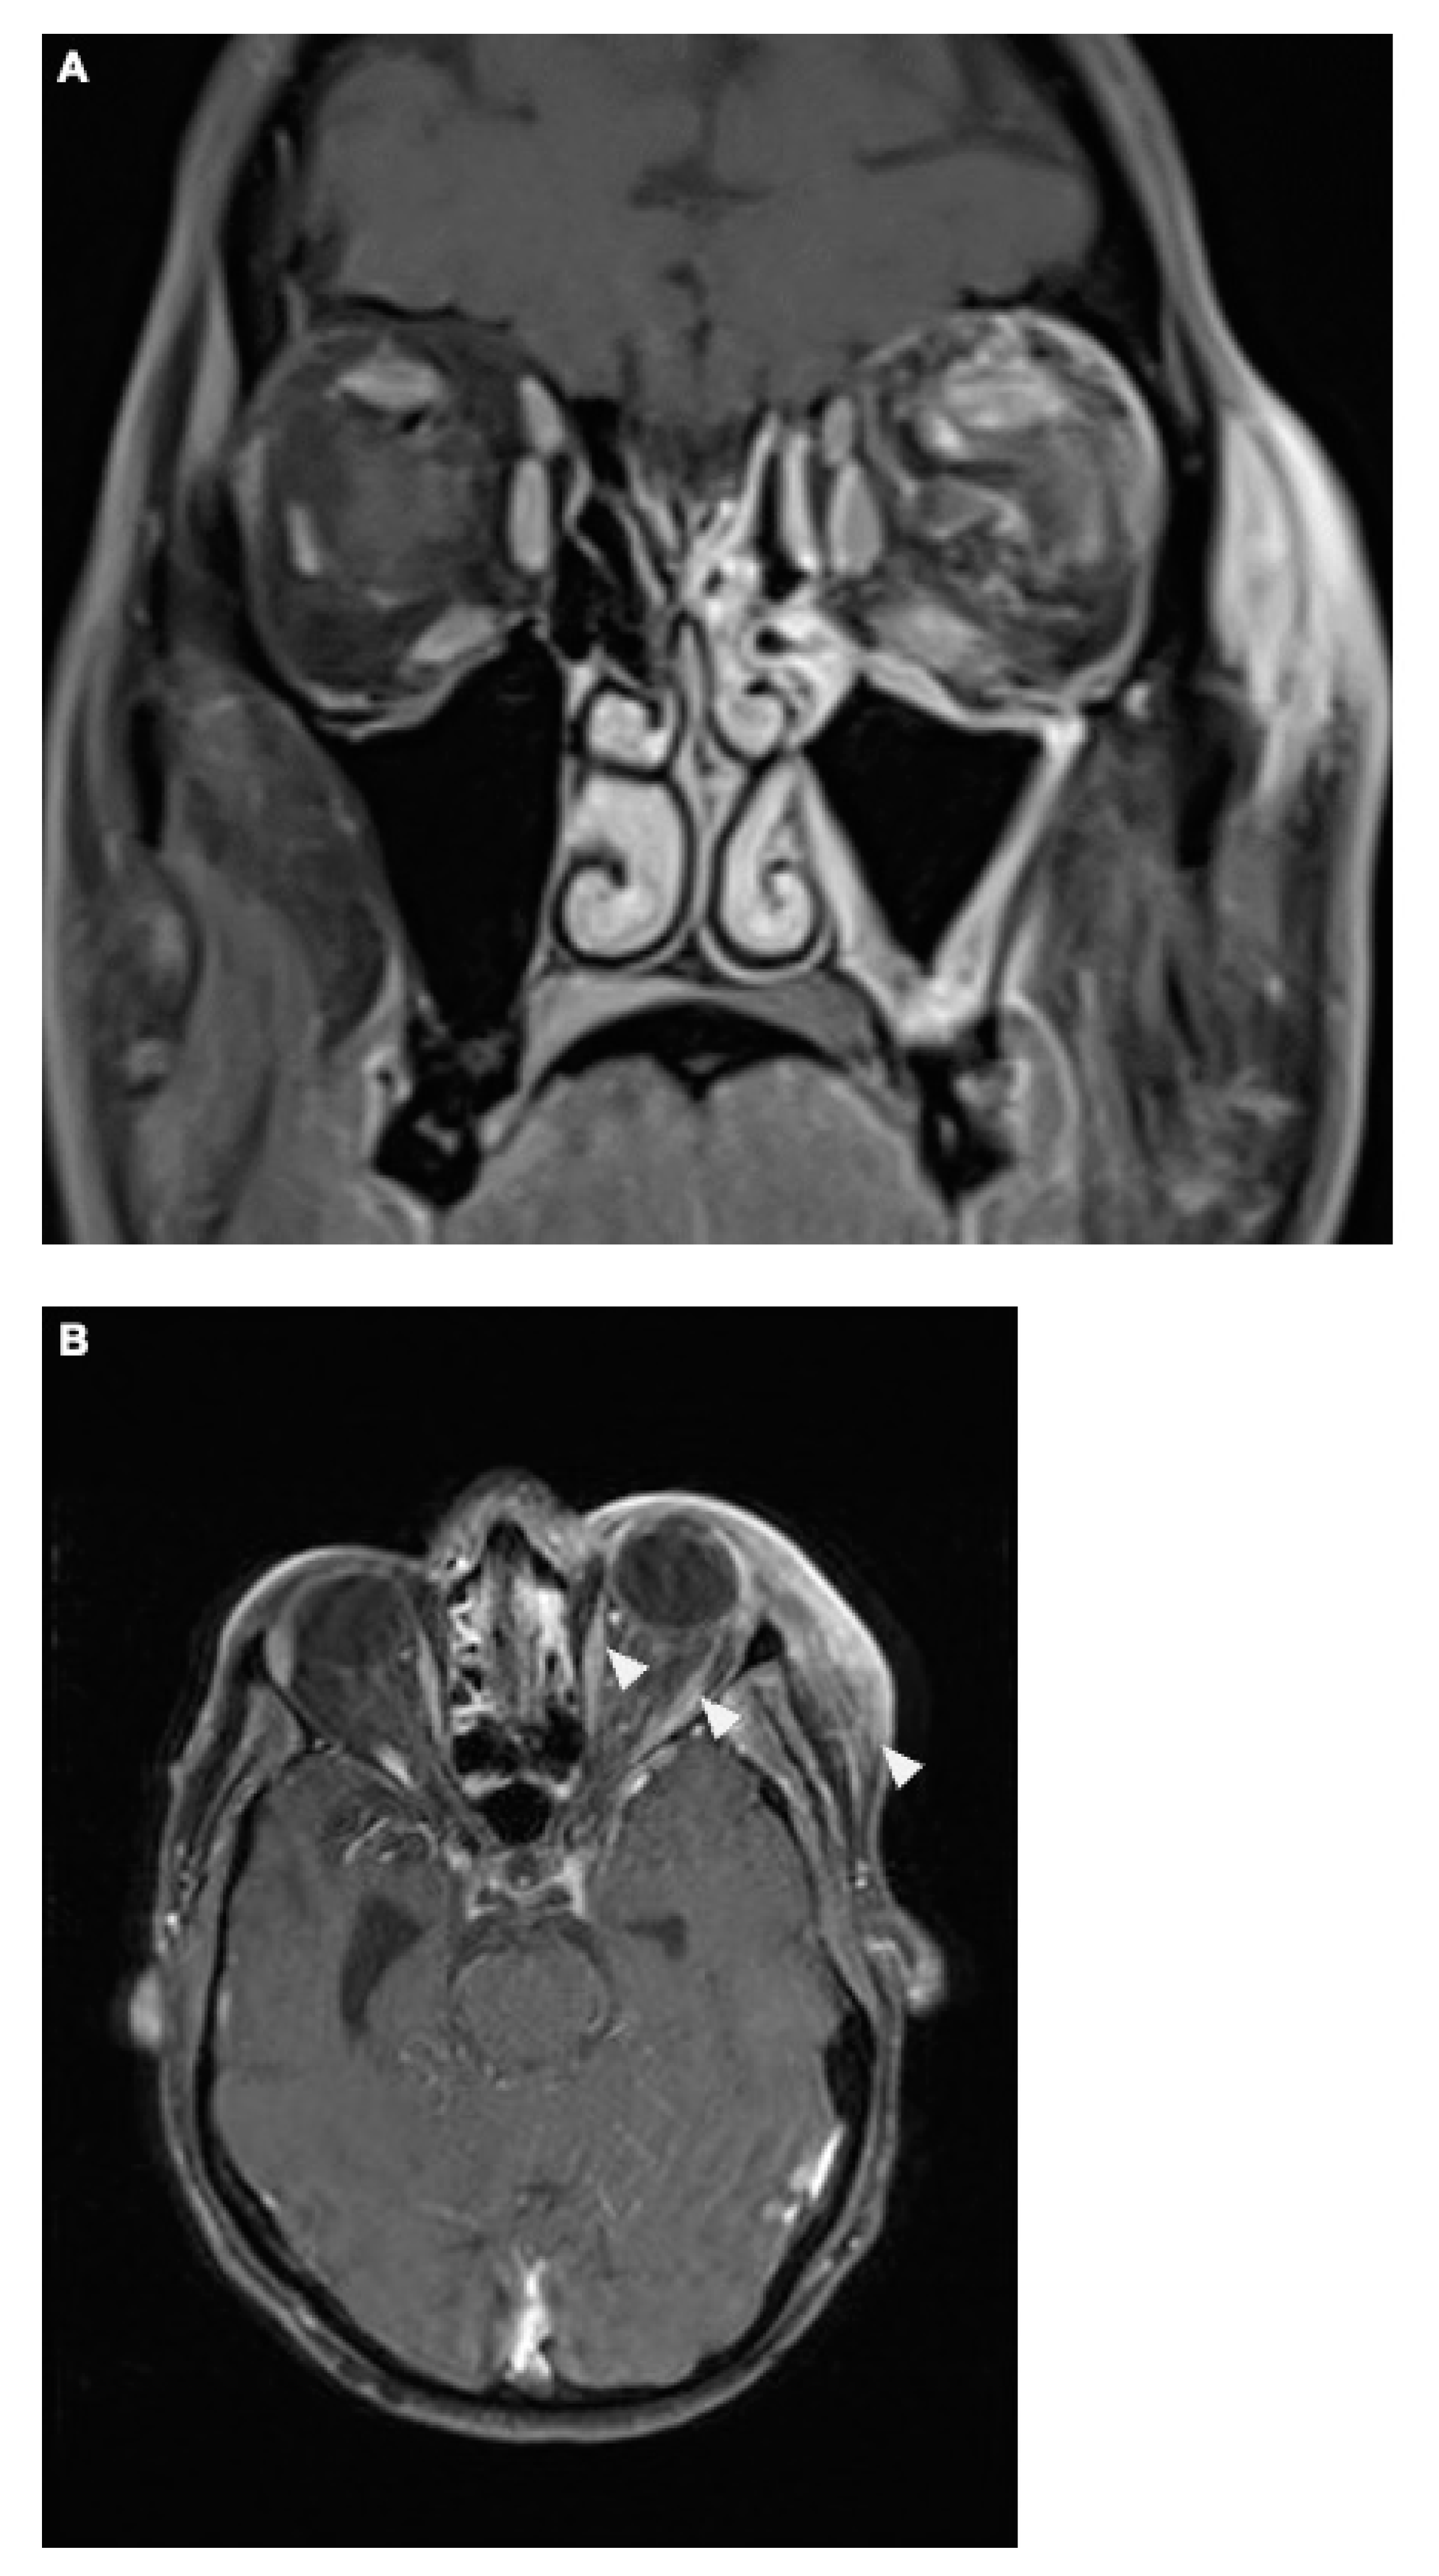

Figure 4.

The coronal T1-weighted post-Gadolinium magnetic resonance imaging (MRI) sequence revealed no definitive evidence of cavernous sinus thrombosis. However, venous dilation in the left superior ophthalmic vein was noted, along with significant phlegmonous enhancement at the apex of the left orbit, involving the left superior rectus muscle and potentially the optic nerve. Adjacent sinusitis was observed in the left frontal, ethmoid, sphenoid, and maxillary sinuses, accompanied by mild swelling of the left eyelid and inflammation of the adjacent subcutaneous tissue (A). The axial T1 post-Gadolinium MRI sequence (B) demonstrated contrast-enhanced protrusion of the left eye muscles, particularly affecting the superior rectus muscle. This indicated ongoing inflammation, though there was a slight reduction in the extent of optic nerve involvement compared to earlier scans, suggesting a partial therapeutic response. Importantly, no signs of cavernous sinus thrombosis were observed (as described above), and the venous structures remained patent.

Under corticosteroid therapy, there was no improvement in the patient’s symptoms, particularly the local swelling, and the complete ophthalmoplegia persisted. Instead, following the initiation of corticosteroids, the patient developed additional neurological symptoms, including fluctuating episodes of aphasia as well as mild right-sided hemiparesis (National Institutes of Health Stroke Scale [NIHSS] 7 points) starting on day 3 of the treatment. Therefore, cerebral CT with CTA was repeated and showed no significant changes compared to the initial scan on the day of admission (as described in Figure 2A,B), except that the soft tissue swelling appeared to be more pronounced now. Additional cerebral magnetic resonance imaging (MRI) did not reveal any diffusion restrictions. Multiple small white matter lesions were identified bilaterally in the periventricular regions, likely indicative of chronic microangiopathic changes. Symmetrical calcifications in the thalami were consistent with findings from the previous CT scan. The MRI also confirmed the right temporal defect with ex vacuo dilation of the temporal horn. Regarding the local symptoms, venous dilation in the left superior ophthalmic vein was noted, along with significant phlegmonous enhancement at the apex of the left orbit, involving the left superior rectus muscle and potentially the optic nerve. Adjacent sinusitis was observed in the left frontal, ethmoid, sphenoid, and maxillary sinuses, accompanied by mild swelling of the left eyelid and inflammation of the adjacent subcutaneous tissue as well as contrast-enhanced protrusion of the left eye muscles (Figure 4).